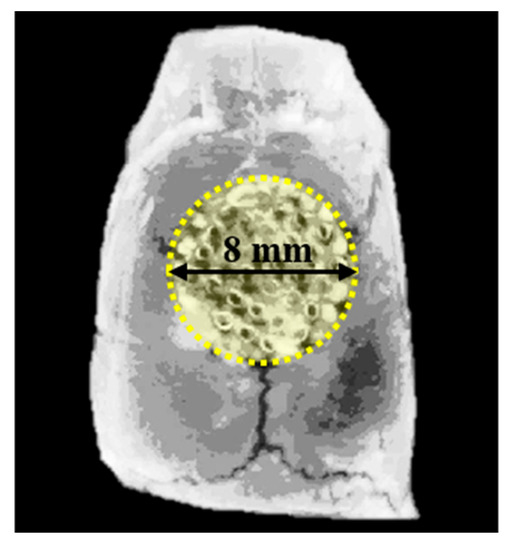

All the specimens of 3D Hexahedron Channeled synthetic block bone were supplied (BoneplantTM, Ezekiel, Chungchung-Namdo, Korea) after sterilization using gamma irradiation. The 3D hexahedron channeled bone block was made of BCP microporous ceramics, with a mixture of 60% HA and 40% β-TCP. The pore size of the disc-shaped bone block (diameter: 8 mm, thickness: 2 mm) was 400–700 μm with 95% porosity (Figure 1). Prior to the animal experiment, the bone blocks were coated with 100 μL of CMC (1.5%, CowellMedi, Busan, Korea) or CMC containing 5 μg of rhBMP-2 (CowellMedi, Busan, Korea) in a completely sterile laboratory [39,46]. The low-level sonication was performed to uniformly coat CMC on the Boneplant surface. The experimental groups of this study were as below:

Figure 1. The images of BCP block bone with a 3D hexahedron channel. (a) Top view; (b) top-side view.

To measure the new bone volume within the defect area, the specimens were imaged by micro-computed tomography (SMX-90CT, Shimadzu, Kyoto, Japan) at 90 kV, at an intensity of 109 μA. The region of interest (ROI) was set equal to bony defect size (diameter of 8 mm, height of 1.5 mm) (Figure 3). The images distinguished mineralized bone, soft tissues, and scaffold by adjusting the threshold. The percentages of new bone volume were calculated by customized program corded by cording software (MATLAB 2018a, MathWorks, Natick, MA, USA).

Figure 3. Region of interest (ROI) for micro-computed tomography (μCT) analysis.